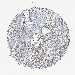

STOMACH CANCER - Protein expressioni

A mouse-over function shows sample information and annotation data. Click on an image to view it in a full screen mode. Samples can be filtered based on level of antibody staining by selecting one or several of the following categories: high, medium, low and not detected. The assay and annotation is described here.

Note that samples used for immunohistochemistry by the Human Protein Atlas do not correspond to samples in the TCGA dataset.

Antibody stainingi

Antibody staining in the annotated cell types in the current human tissue is reported as not detected, low, medium, or high, based on conventional immunohistochemistry profiling in selected tissues. This score is based on the combination of the staining intensity and fraction of stained cells.

Each image is clickable and will lead to virtual microscopy that enables deeper exploration of all samples and also displays staining intensity scores, fraction scores and subcellular localization as well as patient and tissue information for each sample.

Antibody HPA018951

Antibody CAB013716

Staining

High

Medium

Low

Not detected

Intensity

Strong

Moderate

Weak

Negative

Quantity

>75%

75%-25%

<25%

None

Location

Nuclear

Cytoplasmic/membranous

Cytoplasmic/membranous,nuclear

Adenocarcinoma, NOS

Adenocarcinoma, High grade